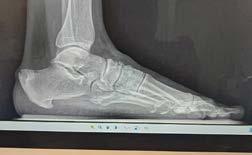

ESPOLÓN CALCÁNEO Y FASCITIS PLANTAR DOS AFECCIONES COMUNES DEL PIE - P. 72